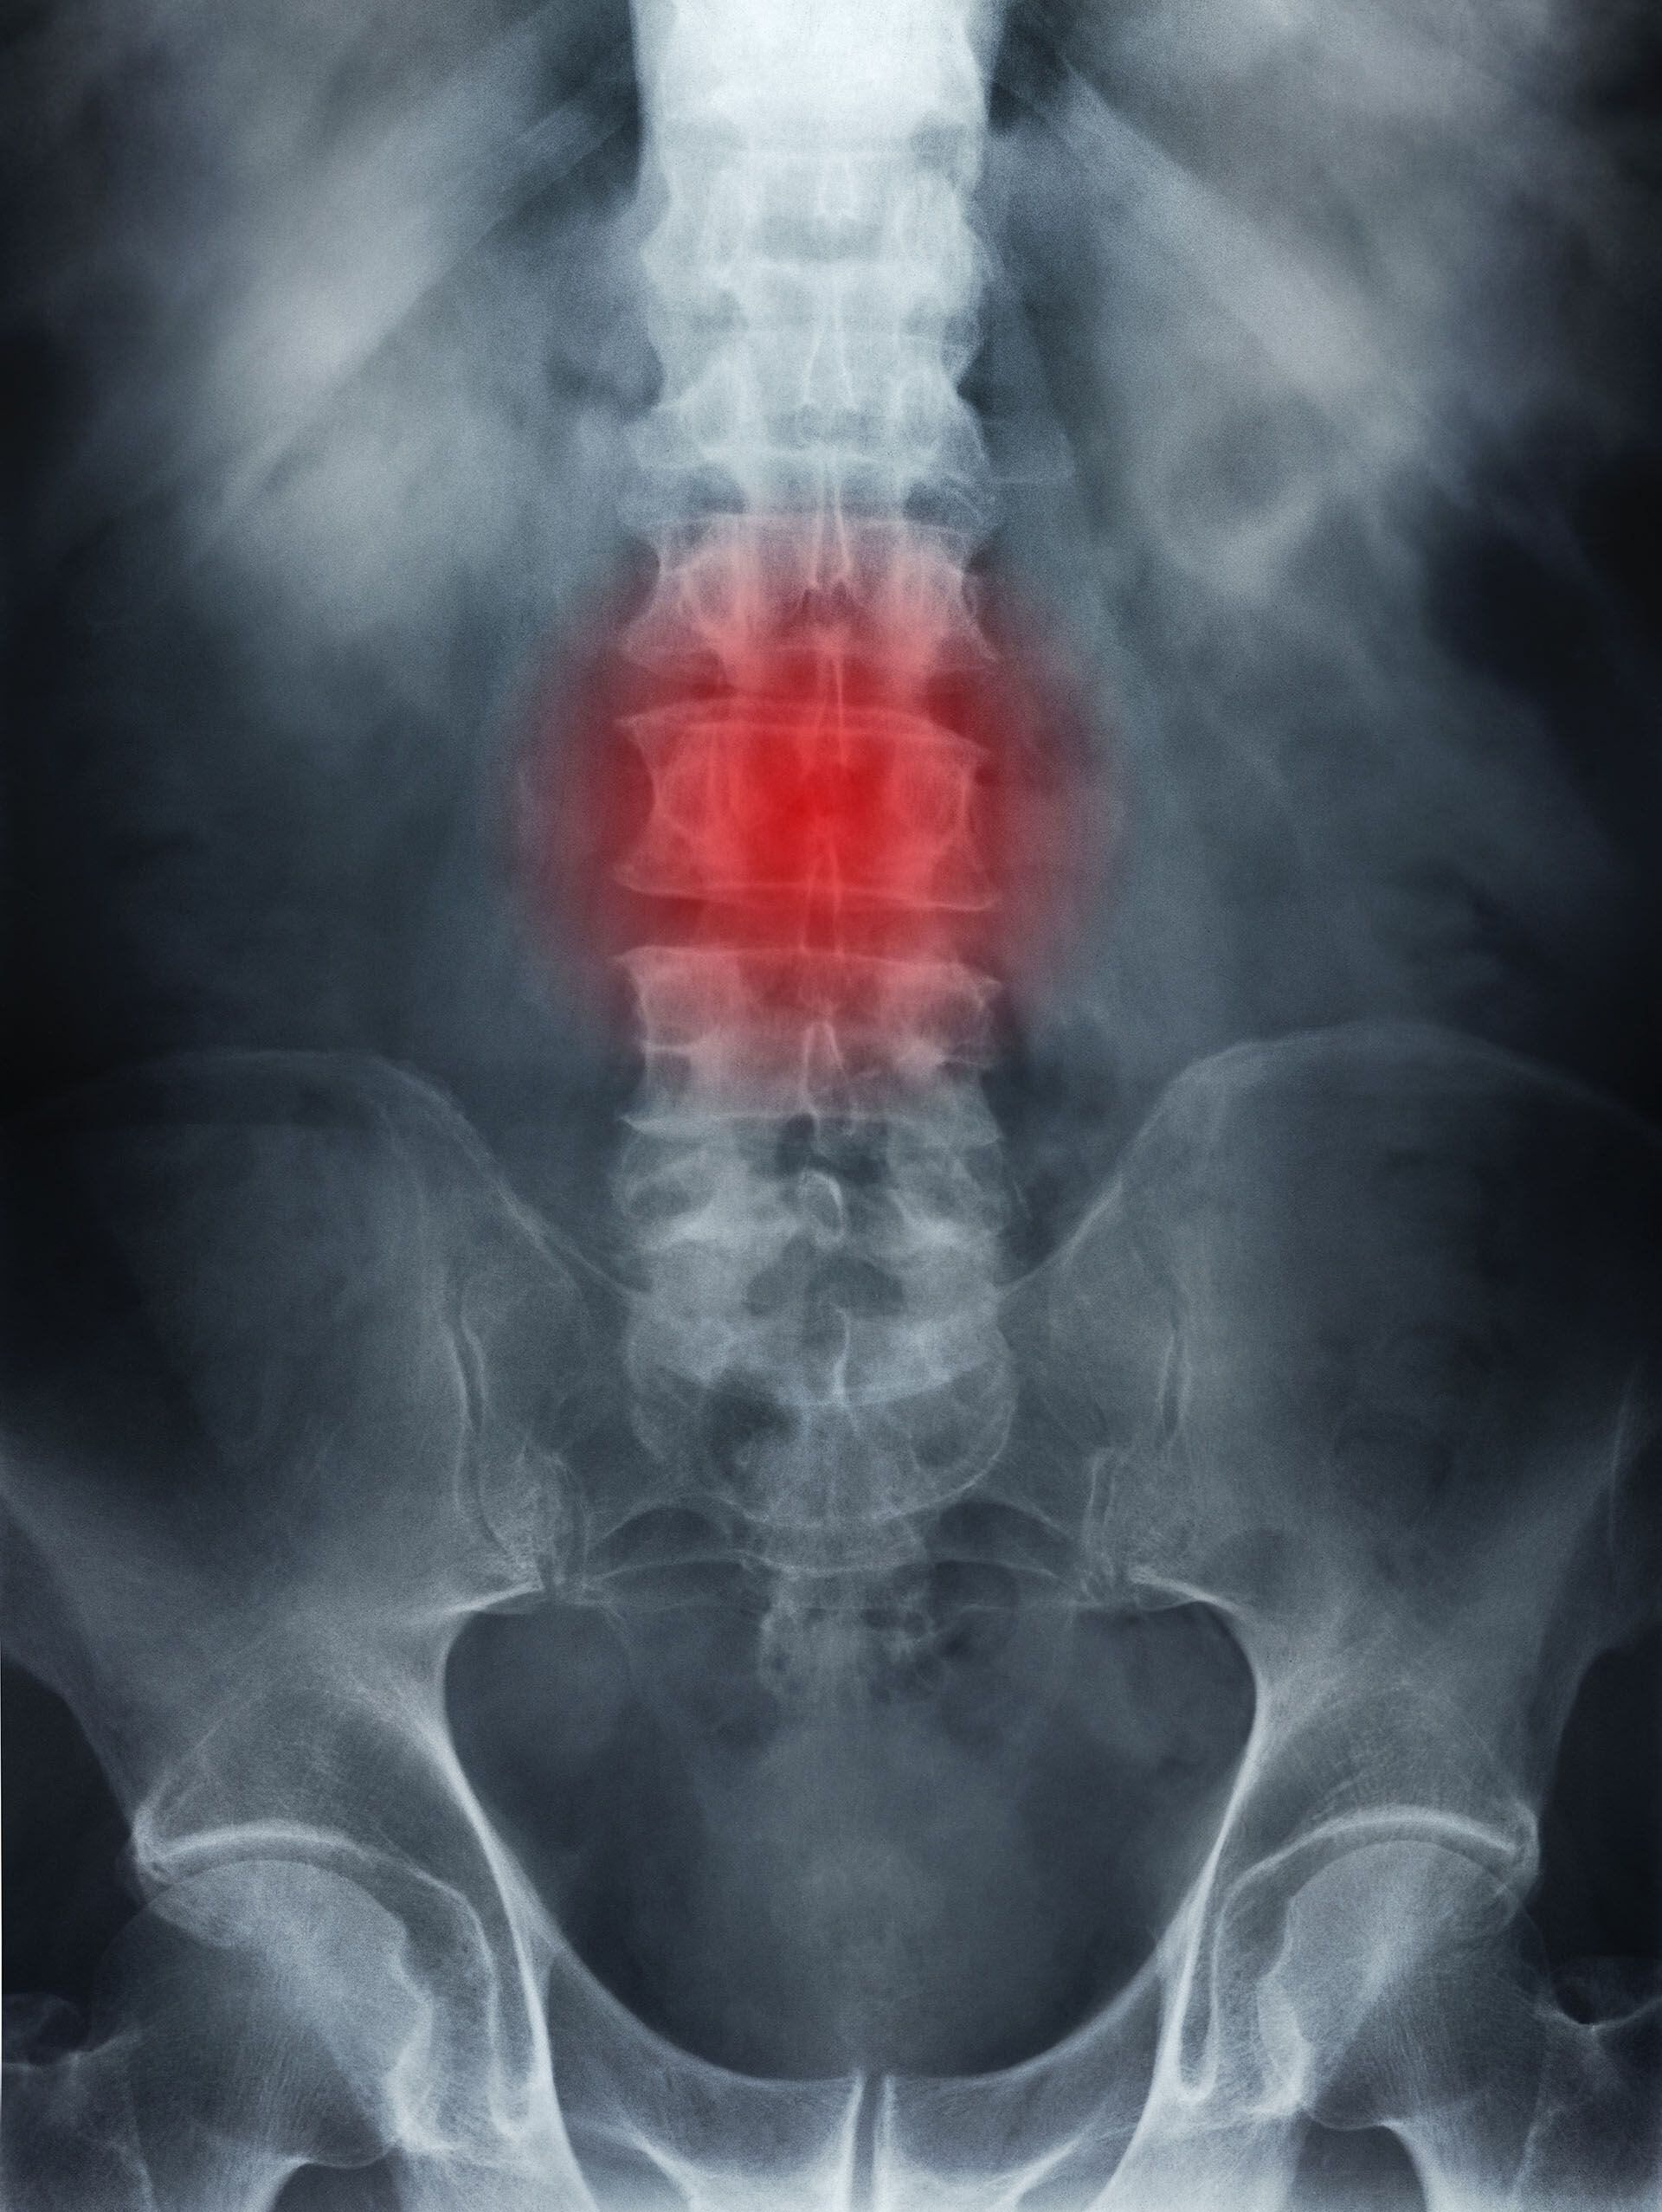

La osteoporosis es una enfermedad silenciosa, que afecta a todo el cuerpo, haciendo que los huesos se vuelvan frágiles. Se trata de una afección que no presenta síntomas visibles, por lo que las personas que la padecen generalmente no lo saben hasta que sufren una fractura.

Los huesos se vuelven más frágiles y un golpe o caída puede ocasionar en una fractura. La osteoporosis afecta a todos los huesos del cuerpo. Sin embargo las fracturas se producen con mayor frecuencia en la cadera, las vértebras y las muñecas. También son frecuentes las fracturas de pelvis y de la parte superior del brazo”, explicó a Infobae la doctora Adriana Díaz, jefa de la Sección Osteopatías del Hospital de Clínicas de la UBA.

-Dolor de espalda, provocado por una vértebra fracturada o aplastada